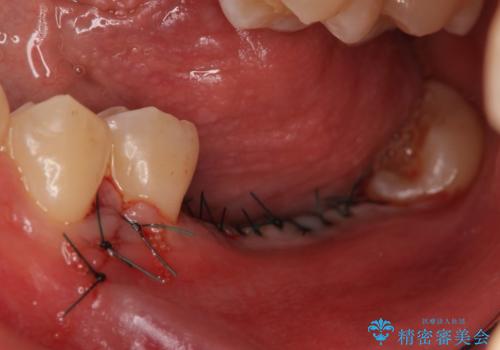

- 数年前に左下の奥歯を2本失ってから物が咬めないため何とかして欲しいと当院にいらっしゃった方の症例です。

左下にインプラント(ストローマン)を2本埋入し、オールセラミッククラウンによる補綴を行いました。